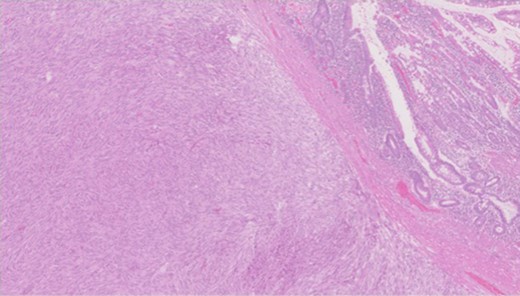

Pathology—GIST of spindle cell type (Figs 3 and 4), 90 mm in size, with complete local excision. Mitotic count—3 per 5 mm square. CD117 (Fig. 5) and DOG1 (Fig. 6) positive staining giving a prognostic group of moderate risk (Miettinen’s classification) of progressive disease. It is widely accepted that Interstitial Cells of Cajal (ICC) are pace maker cells of the gut and probable progenitor cells of GIST. Hyperplasia of ICC can be seen in cases with NF1, however, in this case this could not be shown in the background bowel (Fig. 7).

MNF staining the epithelium of the bowel while is negative in tumour cells.